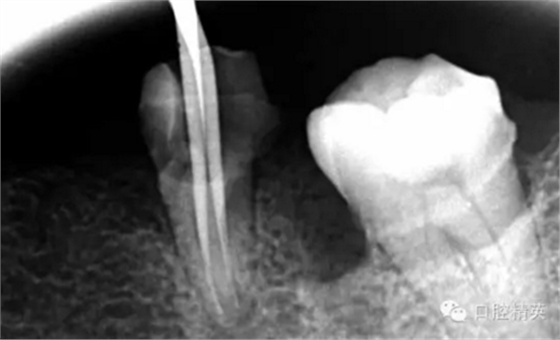

疏通其余三根30分鐘。

近中試尖,超出,這是沒有很好的把握工作長度,這是自己在預備時可能出現(xiàn)超預備的情況,所以以后機括預備一定要注意,防止超預備,否則會導致術(shù)后疼痛。